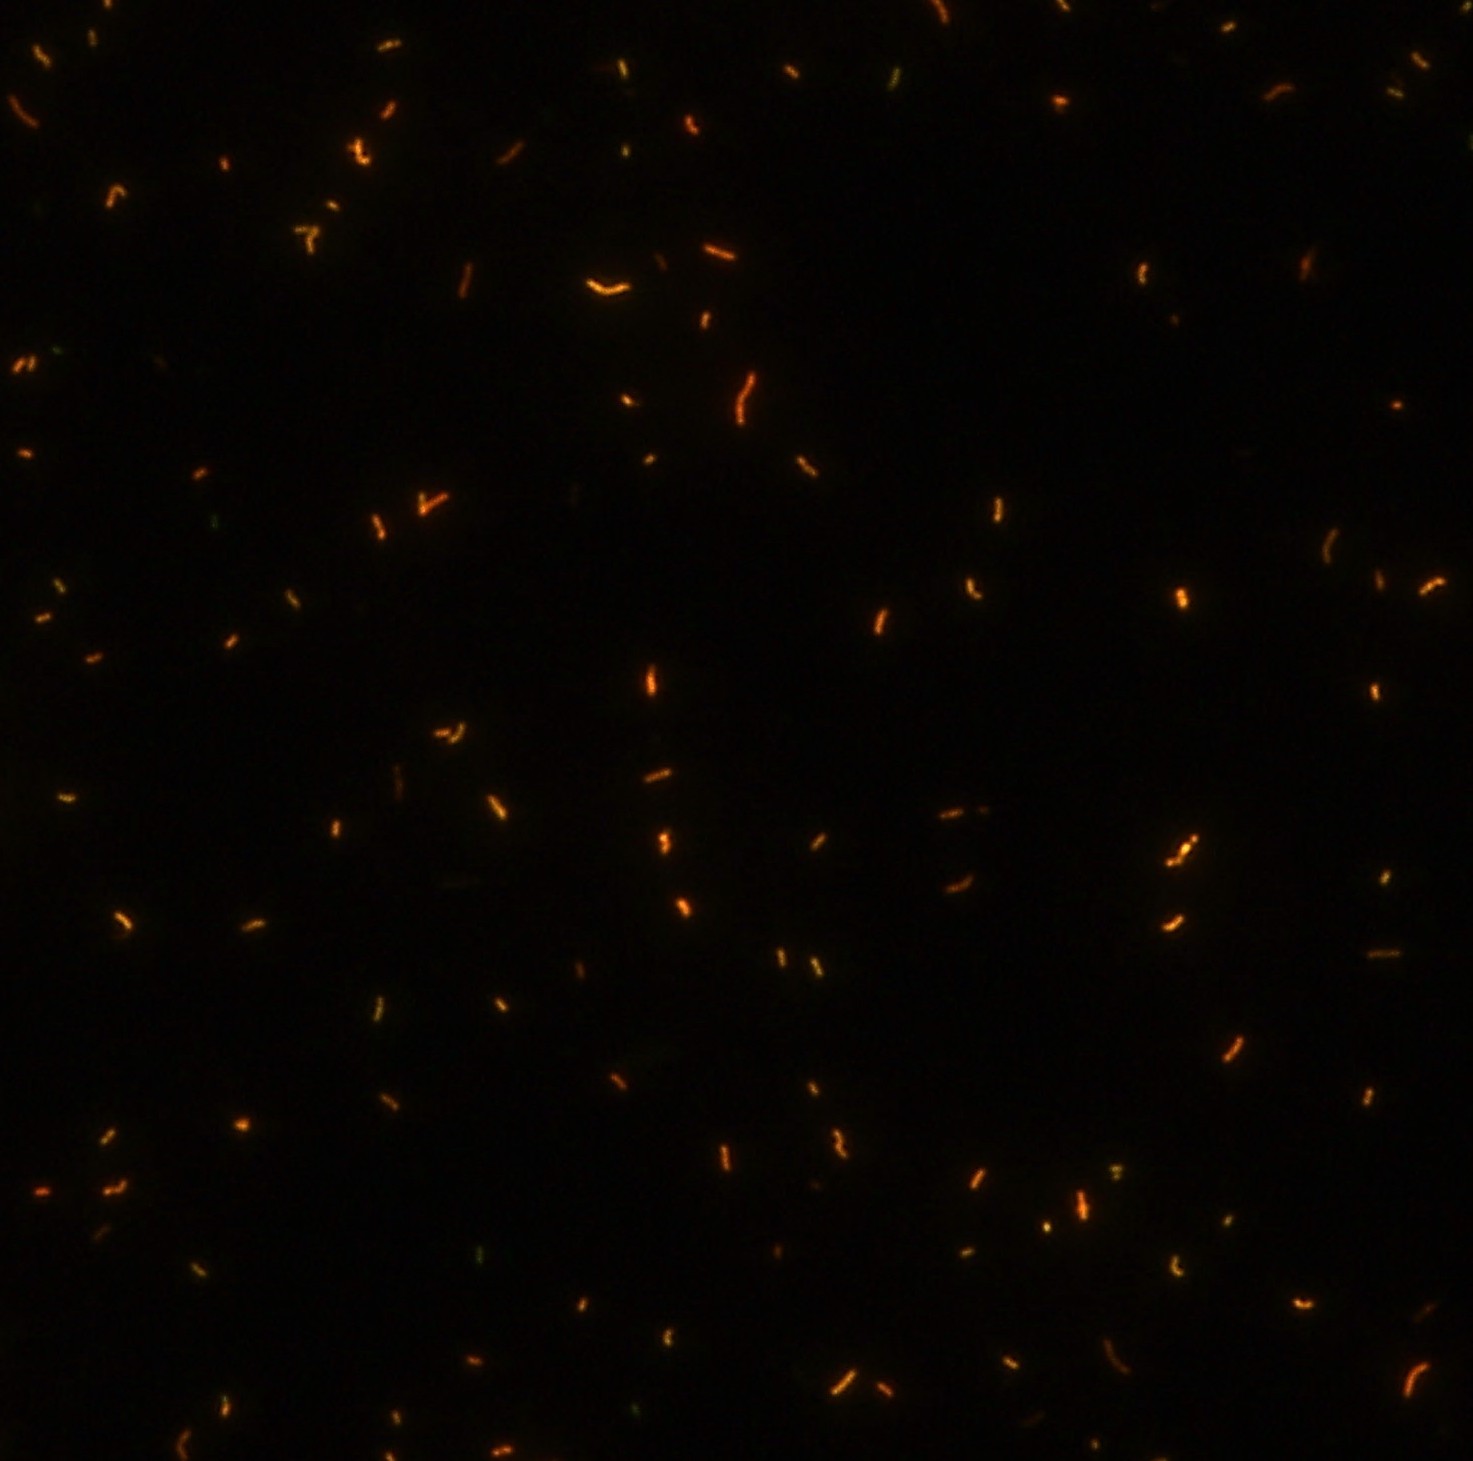

Dagatron抗酸染色液(FR-2A)

顯微染色技術(shù)是檢測結(jié)核桿菌方法之一。分枝桿菌細(xì)胞壁中含有分枝菌酸,其可以與染料牢固結(jié)合,具有“抗酸性”的特征。熒光染料金胺-羅丹明在染色中與抗酸生物細(xì)胞壁內(nèi)的分菌酸相結(jié)合,并耐受酸醇(脫色劑)清洗脫色。反染色劑高錳酸鉀被用來顯出染色生物。AFB(熒光)染色試劑盒設(shè)計既可用于染色機(jī),也可用于手工染色。產(chǎn)品穩(wěn)定性好,染色效果佳。

染色結(jié)果 熒光法×400

用于分枝桿菌、諾卡菌等細(xì)菌抗酸染色,包括熒光染色。